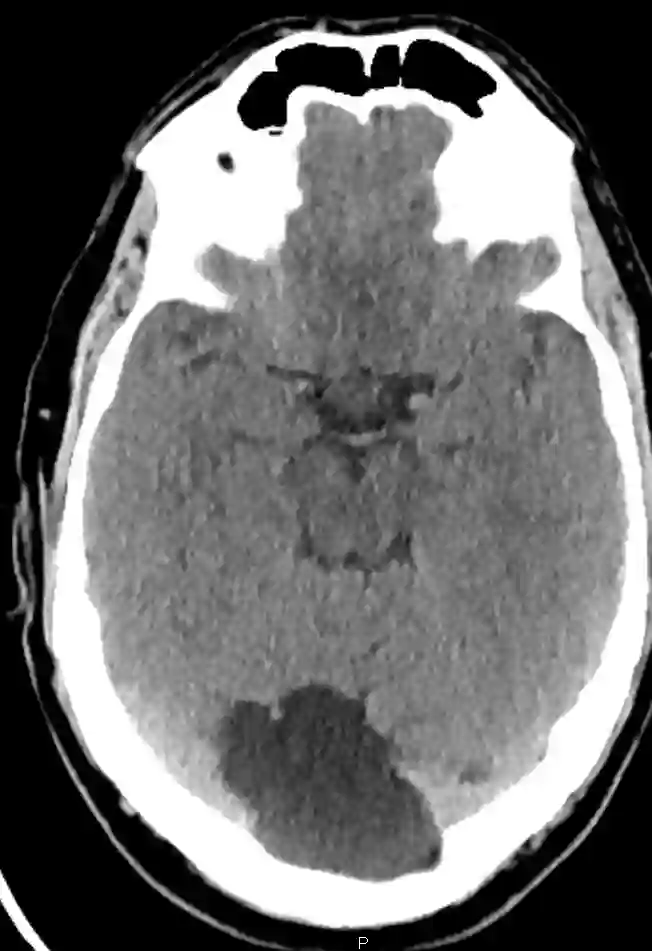

Bildgebung

Arachnoidalzysten können in der CT als auch MRT Bildgebung visualisiert werden.

Occipitale Arachnoidalzyste im CT.

Occipitale Arachnoidalzyste im axialen CT Bild